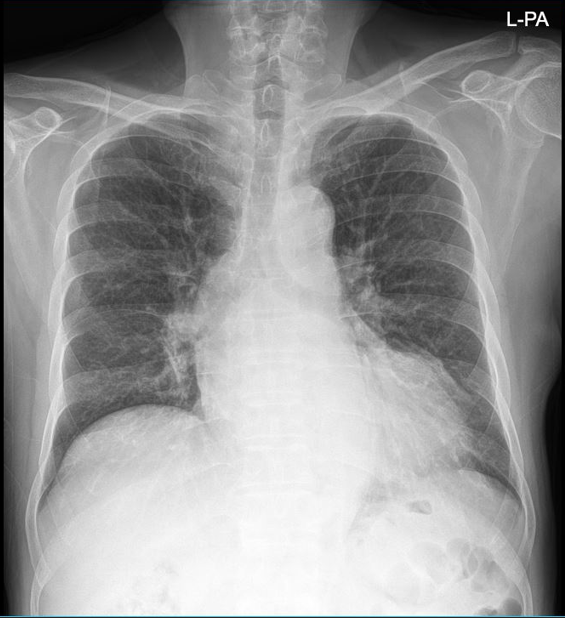

Several investigations were performed to prepare the 67-year-old patient for repeat coronary angiography, with plan for DCB or PCI if required. The team carefully reviewed her clinical stability, cardiac enzymes and imaging results to decide the safest path forward. Each step reflected both urgency and hope to restore her coronary flow and prevent another critical cardiac event from threatening her recovery.

A covered stent was deployed in the distal LAD in an attempt to seal the coronary perforation; however, angiography showed that the Type III perforation persisted despite the intervention. Additional balloon inflation within the stent was performed, but the leakage could not be completely sealed. The patient remained hemodynamically stable without signs of cardiac tamponade or pericardial effusion. The following day, repeat coronary angiography was conducted to reassess the condition, which confirmed persistent contrast extravasation from the LAD into the left ventricular cavity, indicating the formation of a coronary–ventricular fistula. Given the hemodynamic significance and the risk of progressive left ventricular dysfunction due to continuous shunting, a multidisciplinary decision was made to proceed with surgical correction. The patient subsequently underwent successful LAD–LV fistula patch repair combined with. Surgical repair remains the definitive management for such cases, and early recognition with timely intervention is crucial to restore cardiac function and prevent irreversible myocardial damage.